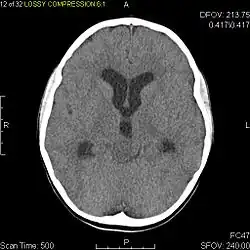

Axial non-contrast CT in a nine-year-old girl showing a slightly hypodense mass in the tectum of the brainstem, compressing the aqueduct of Sylvius and causing obstructive hydrocephalus

Sagittal T1-weighted MRI showing a well-circumscribed hypointense mass in the tectum (presumably a tectal plate glioma). These lesions are a distinct subset of pilocytic astrocytoma which present with hydrocephalus typically in 6 to 10 year-olds and are rarely progressive lesions. When imaging is characteristic, a biopsy is usually not performed because of the risks to adjacent structures, often shunting to relieve intracranial pressure is the only treatment required.